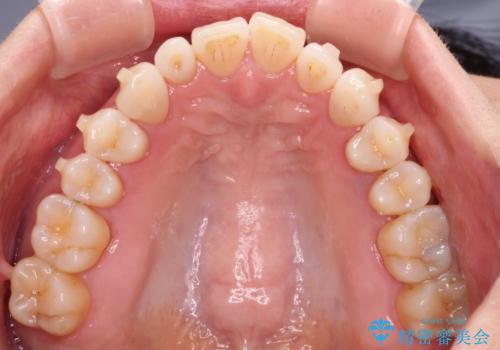

前歯のスペースが気になる インビザラインによる矯正治療

- 前歯の上下スペースによる食べにくさを気にして来院された患者様です。

インビザラインにより上下の前歯の隙間を閉じていくこととしました。

舌の突出癖があると上下前歯にスペースが開くため、矯正治療を機会に舌癖を改善するトレーニングを行ってもらい、矯正治療後の後戻りを防止するように指導しています。